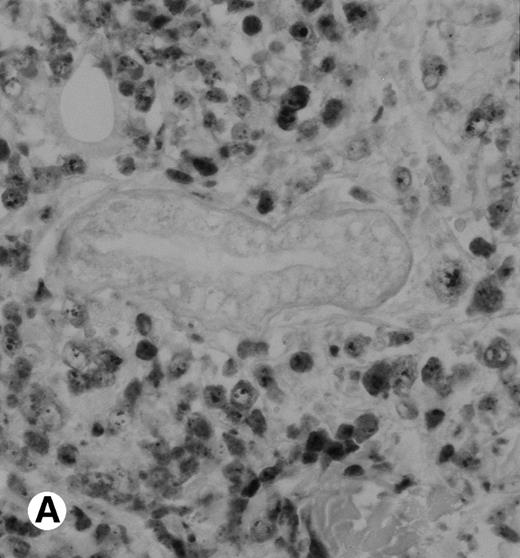

The polyclonal anti-p80 provided a staining of some large cells of 1 of the 11 LyP (case no. 4). A cytoplasmic staining of lymphomatous cells was also seen in 4 of the 15 CD30+ primary CTCL (cases no. 5, 6, 8, and 9) and in 3 of the 11 CD30+ secondary cutaneous lymphomas (cases no. 1, 2, and 3). Keratinocytes or dendritic cells of the dermis were sometimes stained by anti-p80. All p80+ cases were previously shown to contain NPM-ALK transcripts by nested RT-PCR. However, not all cases with NPM-ALK chimeric transcripts were stained by p80+. No p80+ cells were detected in MF and BID sections. The staining with the monoclonal ALK1 antibody was cytoplasmic and nucleolar and restricted to tumoral cells of CD30+lymphomas. Only 1 case of CD30+ primary CTCL was ALK1+ (case no. 8; Fig 3). This case was 1 of the 2 cases with a positive standard RT-PCR amplification, whereas the other 1 was found to be negative for both p80 and ALK1 immunostaining (case no. 10). The 3 cases of CD30+ secondary CTCL with NPM-ALK transcripts were stained for ALK1 (cases no. 1, 2, and 3; Fig 3). No ALK1-immunoreactive cell was found in LyP sections and no labeling of the epidermis was observed. None of the cases with a negative NPM-ALK detection by RT-PCR and none of the MF and BID was found to be stained for ALK1.

Immunohistochemical detection of chimeric NPM-ALK protein (×400). A case of CD30+ primary CLCL (case no. 8; A) and a case of CD30+ secondary CLCL (case no. 1; B) both with a positive NPM-ALK amplification by both RT-PCR and DNA-PCR were stained with the monoclonal ALK1 antibody. A granular cytoplasmic and strong nucleolar staining was observed on the large lymphomatous cells in these 2 cases.